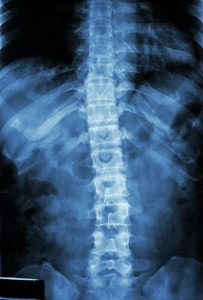

Uit de gezondheidsenquête van het Wetenschappelijk Instituut Volksgezondheid uit 2013 blijkt dat één Belg op vijf een probleem aan de rug signaleert. Eén Belg op acht heeft te kampen met nekproblemen. Wanneer de pijn ondanks de klassieke behandelingen blijft aanslepen, wordt aan sommige patiënten een rugoperatie voorgesteld, met de hoop tot volledige genezing te komen. In twee rapporten bekijkt het KCE of deze ingrepen bieden wat ze beloven.

Het eerste rapport gaat na of percutane vertebroplastie of ballonkyfoplastie efficiënter zijn dan een conservatieve behandeling bij wervelcompressiefracturen (VCF). Bij de chirurgische ingrepen wordt een soort cement ingespoten: bij vertebroplastie gebeurt de injectie rechtstreeks in de gebroken wervel, bij een kyfoplastie wordt eerst een ballonnetje in de ingedeukte wervel ingebracht en opgeblazen, waarna de holte met cement wordt opgevuld. Ook qua terugbetaling bestaat er een groot verschil tussen beide technieken. Het cement wordt in beide gevallen terugbetaald (82 euro), maar de kits voor vertebroplastie (500 euro) en kyfoplastie (4000 euro) worden niet terugbetaald. Het ereloon van de arts (300 euro) wordt terugbetaald bij kyfoplastie, maar niet bij vertebroplastie.

wervelkolom grUit studies blijkt dat er weinig verschil in outcome bestaat tussen beide technieken. Op korte termijn verlichten ze de pijn en verbeteren ze de levenskwaliteit, maar hetzelfde resultaat werd bekomen met een gesimuleerde interventie (inspuiting onder lokale verdoving). Het KCE pleit er dan ook voor om bijkomende studies uit te voeren om na te gaan welke subgroepen van patiënten echt baat hebben bij deze ingrepen. Het kenniscentrum pleit er verder voor om de terugbetaling van beide ingrepen gelijk te stellen.

In een tweede studie keek het KCE naar de volledige vervanging van cervicale of lumbale tussenwervelschijven. Tussenwervelprothesen zijn bedoeld ter vervanging van kraakbeenschijven tussen de wervels wanneer deze aangetast zijn en problemen veroorzaken, voornamelijk pijn aan de nek of de lage rug. Dit is een alternatief voor de klassieke behandeling van wervelfusie (arthrodese), waarbij twee of meer wervels aan elkaar gehecht worden met als doel de druk en de daarmee gepaard gaande pijn op de zenuwwortels te verlichten. Bij lagerugprothesen (1800 euro) betaalt het Riziv terug, bij prothesen voor de nek niet (2500 euro).

In theorie heeft de prothese het voordeel dat de wervels hun beweeglijkheid behouden. De onderzoekers vonden echter geen bewijs dat de prothesen beter zijn dan een wervelfusie. Ze verminderen weliswaar de pijn, maar niet meer dan de klassieke wervelfusie. Conclusie van het KCE: er zijn te weinig argumenten beschikbaar om terugbetaling te rechtvaardigen.